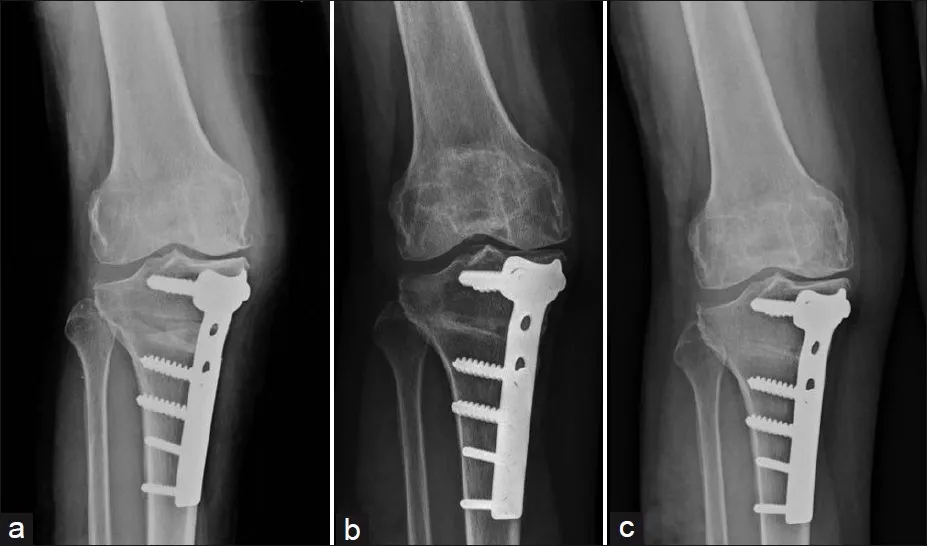

High tibial osteotomy

High Tibial Osteotomy (HTO) is a surgical procedure used

02